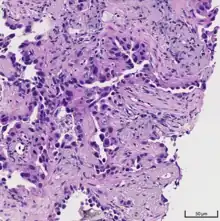

Adenocarcinoma of the lung tends to stain mucin positive as it is derived from the mucus-producing glands of the lungs. Similar to other adenocarcinoma, if this tumor is well differentiated (low grade) it will resemble the normal glandular structure. Poorly differentiated adenocarcinoma will not resemble the normal glands (high grade) and will be detected by seeing that they stain positive for mucin (which the glands produce). Adenocarcinoma can also be distinguished by staining for TTF-1, a cell marker for adenocarcinoma.[29]

As discussed previously, the category of adenocarcinoma includes are range of subtypes, and any one tumor tends to be heterogeneous in composition. Several major subtypes are currently recognized by the World Health Organization (WHO)[1] and the International Association for the Study of Lung Cancer (IASLC) / American Thoracic Society (ATS) / European Respiratory Society (ERS):[30][31][32] lepidic predominant adenocarcinoma, acinar predominant adenocarcinoma, papillary predominant adenocarcinoma, micropapillary predominant adenocarcinoma, solid predominant adenocarcinoma, and solid predominant with mucin production. In as many as 80% of these tumors, components of more than one subtype will be recognized. Surgically resected tumors should be classified by comprehensive histological subtyping, describing patterns of involvement in increments of 5%. The predominant histologic subtype is then used to classify the tumor overall.[2] The predominant subtype is prognostic for survival after complete resection.[33]

To reveal the adenocarcinomatous lineage of the solid variant, demonstration of intracellular mucin production may be performed. Foci of squamous metaplasia and dysplasia may be present in the epithelium proximal to adenocarcinomas, but these are not the precursor lesions for this tumor. Rather, the precursor of peripheral adenocarcinomas has been termed atypical adenomatous hyperplasia (AAH).[10] Microscopically, AAH is a well-demarcated focus of epithelial proliferation, containing cuboidal to low-columnar cells resembling club cells or type II pneumocytes.[10] These demonstrate various degrees of cytologic atypia, including hyperchromasia, pleomorphism, prominent nucleoli.[10] However, the atypia is not to the extent as seen in frank adenocarcinomas.[10] Lesions of AAH are monoclonal, and they share many of the molecular aberrations (like KRAS mutations) that are associated with adenocarcinomas.[10]